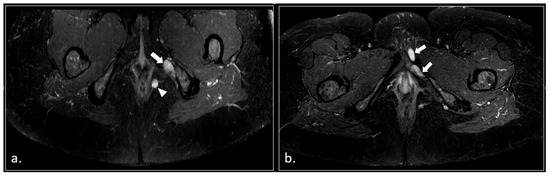

MRI in Chronic Pudendal Neuralgia: Diagnostic Criteria and Associated Pathologies

by Michele Gaeta, Sofia Turturici, Karol Galletta, Carmelo Geremia, Attilio Tuscano, Aurelio Gaeta, Marco Cavallaro, Salvatore Silipigni and Francesca Granata

Diagnostics 2026, 16(2), 326; https://doi.org/10.3390/diagnostics16020326 (registering DOI) - 20 Jan 2026

Background/Objectives: Chronic pudendal neuralgia is a relatively rare condition in the general population, with an incidence of 1%. Although diagnosis of pudendal neuralgia is mainly clinical, Magnetic Resonance Imaging (MRI) is commonly performed to obtain further information. However, clear criteria and guidelines for MRI diagnosis and the clinical–radiological correlation are still not definite. Methods: We reviewed 81 patients with chronic pudendal neuralgia, studied by an MRI designed protocol for a pelvis and pelvic floor examination. A key element of the protocol was the use of a diffusion-weighted imaging (DWI) technique with echo planar imaging (EPI) sequence (b-values of 0, 100, and 600) for the neurographic evaluation of the nerve. Results: MRI examination revealed DWI abnormalities in 42/81 patients. Pudendal nerve abnormalities were unilateral in 33/42 patients and bilateral in 9/42. Moreover, in 23/42 patients, pathologies related to a high probability of neuropathy have been identified. Conclusions: This study highlights the role of pelvic MRI as a valuable imaging modality in the evaluation of patients with chronic pudendal neuralgia. In the study protocol we propose, an essential role is played by the DWI technique, which improves the visual definition of the pudendal nerve and related anatomical structures. By focusing on anatomical visualization and structured image interpretation, our work provides a practical imaging-oriented contribution to a field in which standardized MRI evaluation is still lacking. Full article